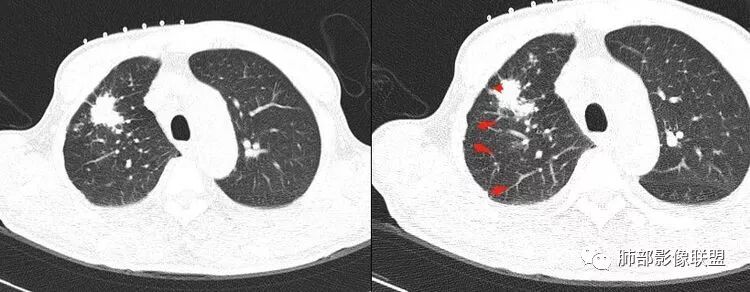

右侧胸廓稍塌陷,右肺体积稍变小,右肺上叶结节,有膨隆有收缩,局部膨隆明显,见胸膜牵拉,胸膜多发增厚,周围卫星灶,另两肺感觉多发微结节影,应该是有结核的,右肺上叶大结节需警惕合并肺腺癌,建议完善增强和三维重建,另两肺多发微结节,有贲门癌病史,需除外转移瘤。

小兜:右肺上叶尖段结节,分叶,周边见细长毛刺及胸膜牵拉,周边多发卫星灶,考虑结核可能性大。

浪迹天涯:老年男性,贲门癌病史,右肺上叶病灶,局部有深分叶,边缘清楚,周围可见多发点状高密度影,邻近胸膜增厚(其脂肪层可见,未被侵犯),1.结核可能性大,2.腺癌合并结核。

2.右肺上叶斑片影、结节影、硬树丫,密度均匀未见钙化或液化。近胸壁处见分叶结节影及棘状突起,胸膜牵拉凹陷。

4.细看病灶有些散,有堆砌感。注意结核灶也常有胸膜牵拉。